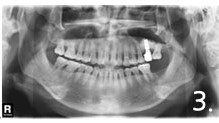

Case #2

Before the surgery. There is not enough bone at back site to place implants

Implant placement and sinus bone graft were performed simultaneously on right side. Only sinus bone graft was performed on left side due to the lack of the residual bone to place implant simultaneously

Implant placement was performed a few months after sinus bone graft

All implant crowns were fabricated and delivered. All teeth functions were restored.